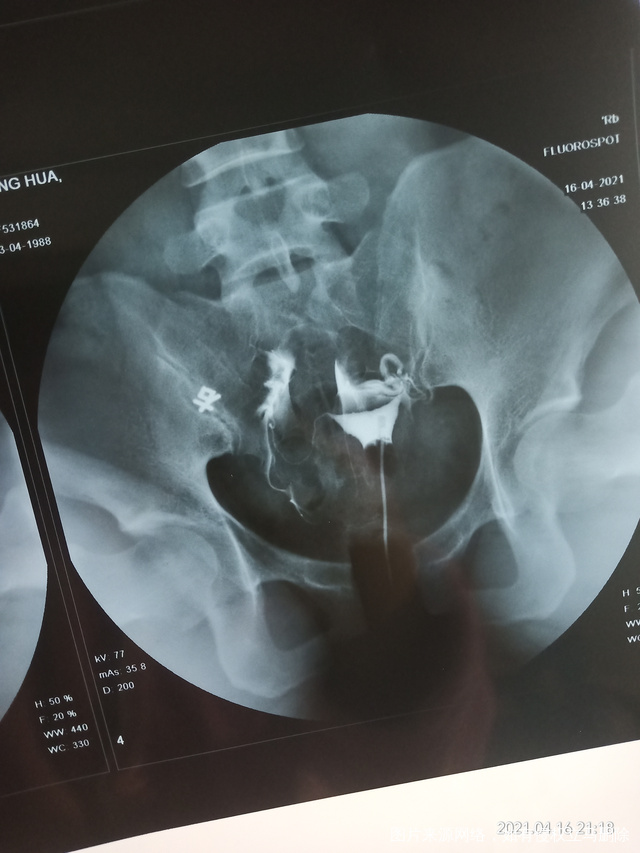

您好麻烦您帮我看看这个片子是什么问题感谢

做完输卵管造影第六天了小腹还是感觉沉甸甸的如

可以热敷腹部,如果有发热,腹痛加剧,白带量多,有异味,随时就医